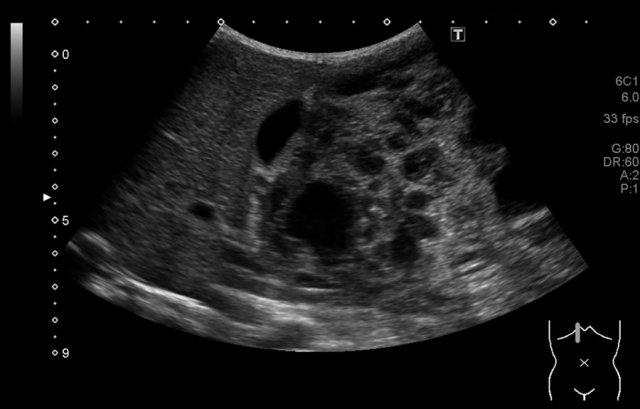

Siêu âm của một bé trai mười lăm tháng tuổi, ban đầu được nghi ngờ có khối u ở thận trái.

Siêu âm cho thấy một khối u nằm kề cực trên phía trong của thận trái. Khối u có vẻ tách biệt với thận. Khối u rất không đồng nhất và có nhiều vôi hóa.

Những phát hiện này phù hợp với u nguyên bào thần kinh hơn là u nguyên bào thận.